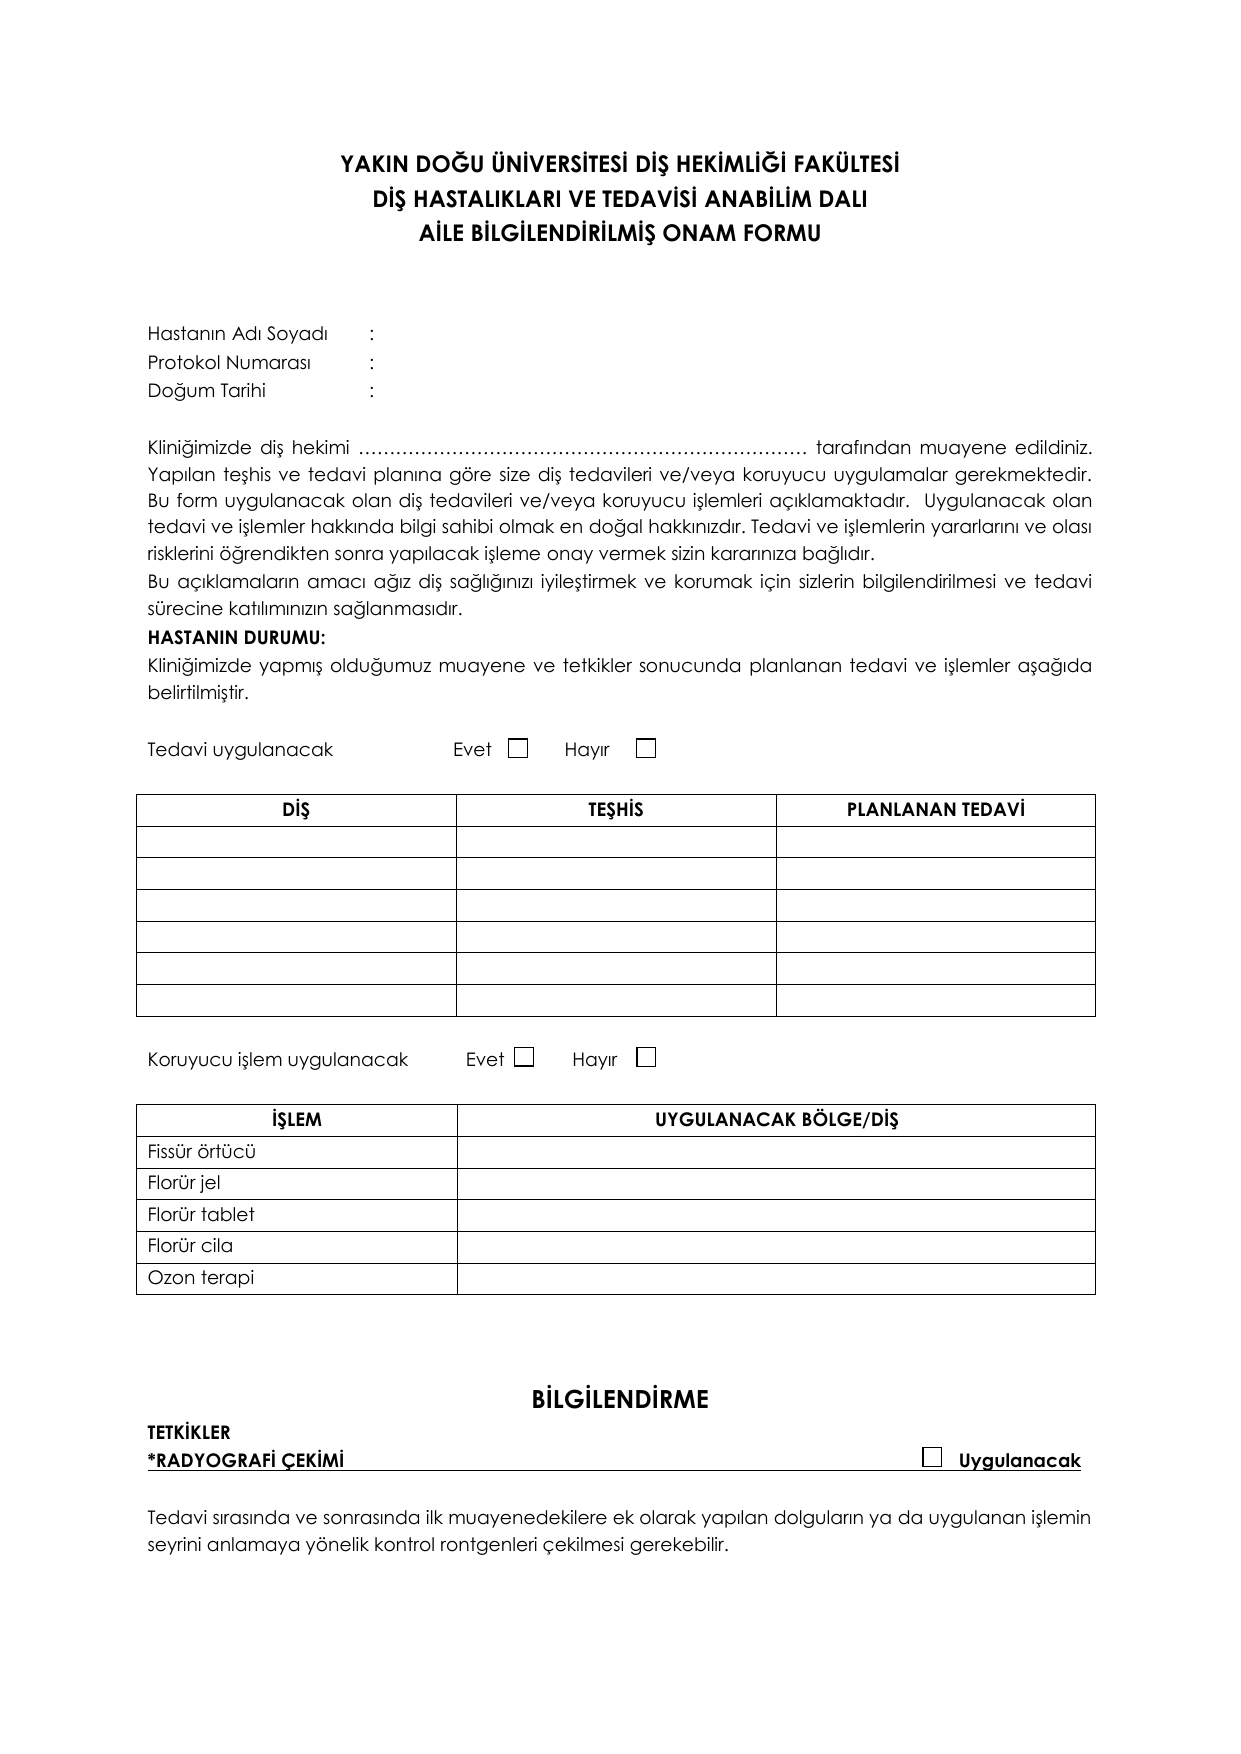

Ozon Tedavisi Diş

Ozon tedavisi diş. Her hastanın sağlık durumuna göre değişen dozlarda ve yine hastanın durumuna göre seçilen yöntemlerle yapılması gereken ozon terapi. Eklem ağrıları kireçlenmeler bel ve boyun fıtıkları fibromiyalji gibi rahatsızlıkların tedavisinde uygulanan bir tedavidir. Ozon terapisi oksijen tedavisi olarak da bilinen enfeksiyonu ortadan kaldırmak ve ilaçların toksik yan etkileri olmadan çevredeki sağlıklı dokuyu desteklemek için oksijeni kullanan bir tedavi şekli olarak da tanımlanabilir. Tıp biliminde de uzun zamandır kullanılmakta olan ozon oksijen bazlı güçlü bir oksidan ajandır.

Günümüzde çürüklerin nazikçe tedavisi artık mümkündür. Ozon diş sağlığında ozon diş hekimliğinde ozon ozon kullanımı diş sağlığı ve ozon ozon tedavisi sitemizde yer alan döküman ve yazılar uzman üyelerimiz tarafından hazırlanmış ve pek çoğu bilimsel düzeyde yapılmış çalışmalar olduğundan güvenilir mahiyette eserlerdir. Pratik uygulamalar da dahil ancak bu konuda eğitim almış olan bir doktor tarafından uygulanabilir. Diş hekimliğinde ozon yeni tedavi protokollerinde yerini almaktadır.

Diş hekimliğinde ozon tedavisi. Ozon antimikrobiyal etkisini hücre bakterilerinin hücre zarında hasar oluşturarak göstermektedir. Ozon sayesinde çürük oluşturan bakteriler ağrı ve anestezi olmadan çok kısa bir sürede tamamen ve güvenilir bir biçimde yok edilir. Ozon tedavisi diğer adı ile oksijen tedavisinin birçok hastalıkta yardımcı tedavi yöntemi olarak sıklıkla tercih edildiğini ifade eden dr.

Ozon terapi özellikle kan yoluyla yapıldığında son derecede titizlikle yapılması gereken bir tedavidir. Diş eksikliklerinizi doğru şekilde telafi etmeniz ve daha sağlıklı ve konforlu dişlere sahip olmanız için diş implant tedavisini ozon terapi desteğiyle veriyoruz tüm i̇mplant tedavisi sadece 1 günde. Hekimin önerileri doğrultusunda uygulandığı takdirde rutin tıbbi tedavinin sonuçlarına herhangi bir etkisinin bulunmaması bu tedavi yönteminin en büyük artılarından. Biran ekici ozon tedavisi hakkında bilgi verdi.